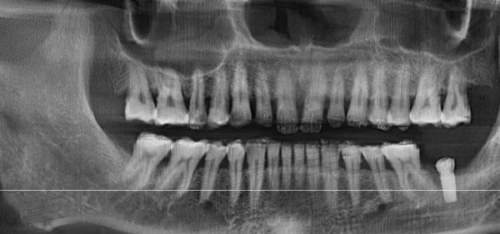

麦特登口腔:价格略高,但定位中高端客户,采用CBCT全景扫描+德国implantec系统,适合精密种牙的吃货党。

硬核设备:引入瑞士Straumann种植系统、数字种植导航系统(拍一张CT图,术前就能看到种好牙后的成效图),机器指导植入路线,连菜鸟医生都能稳准种牙。